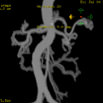

Abd Aorta VR

从外形上显示腹部主动脉及其主要分支血管的起源.走形及其它的形态